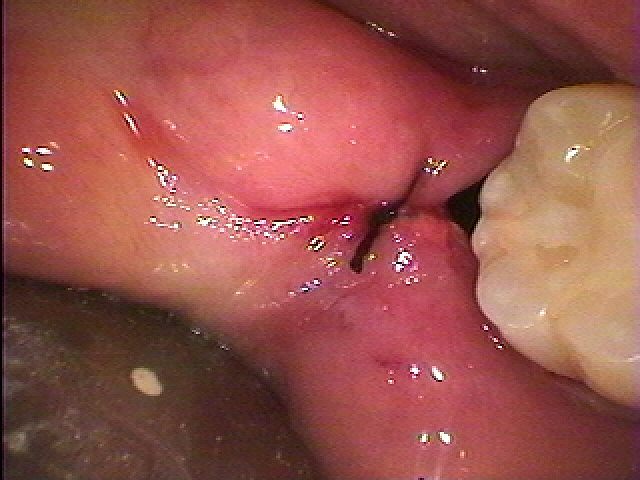

麻酔をかけ歯間部を分割していきます

歯間部がきれいに取れました

出血は全くありません

麻酔をかけ歯間部を分割していきます

歯間部がきれいに取れました

出血は全くありません